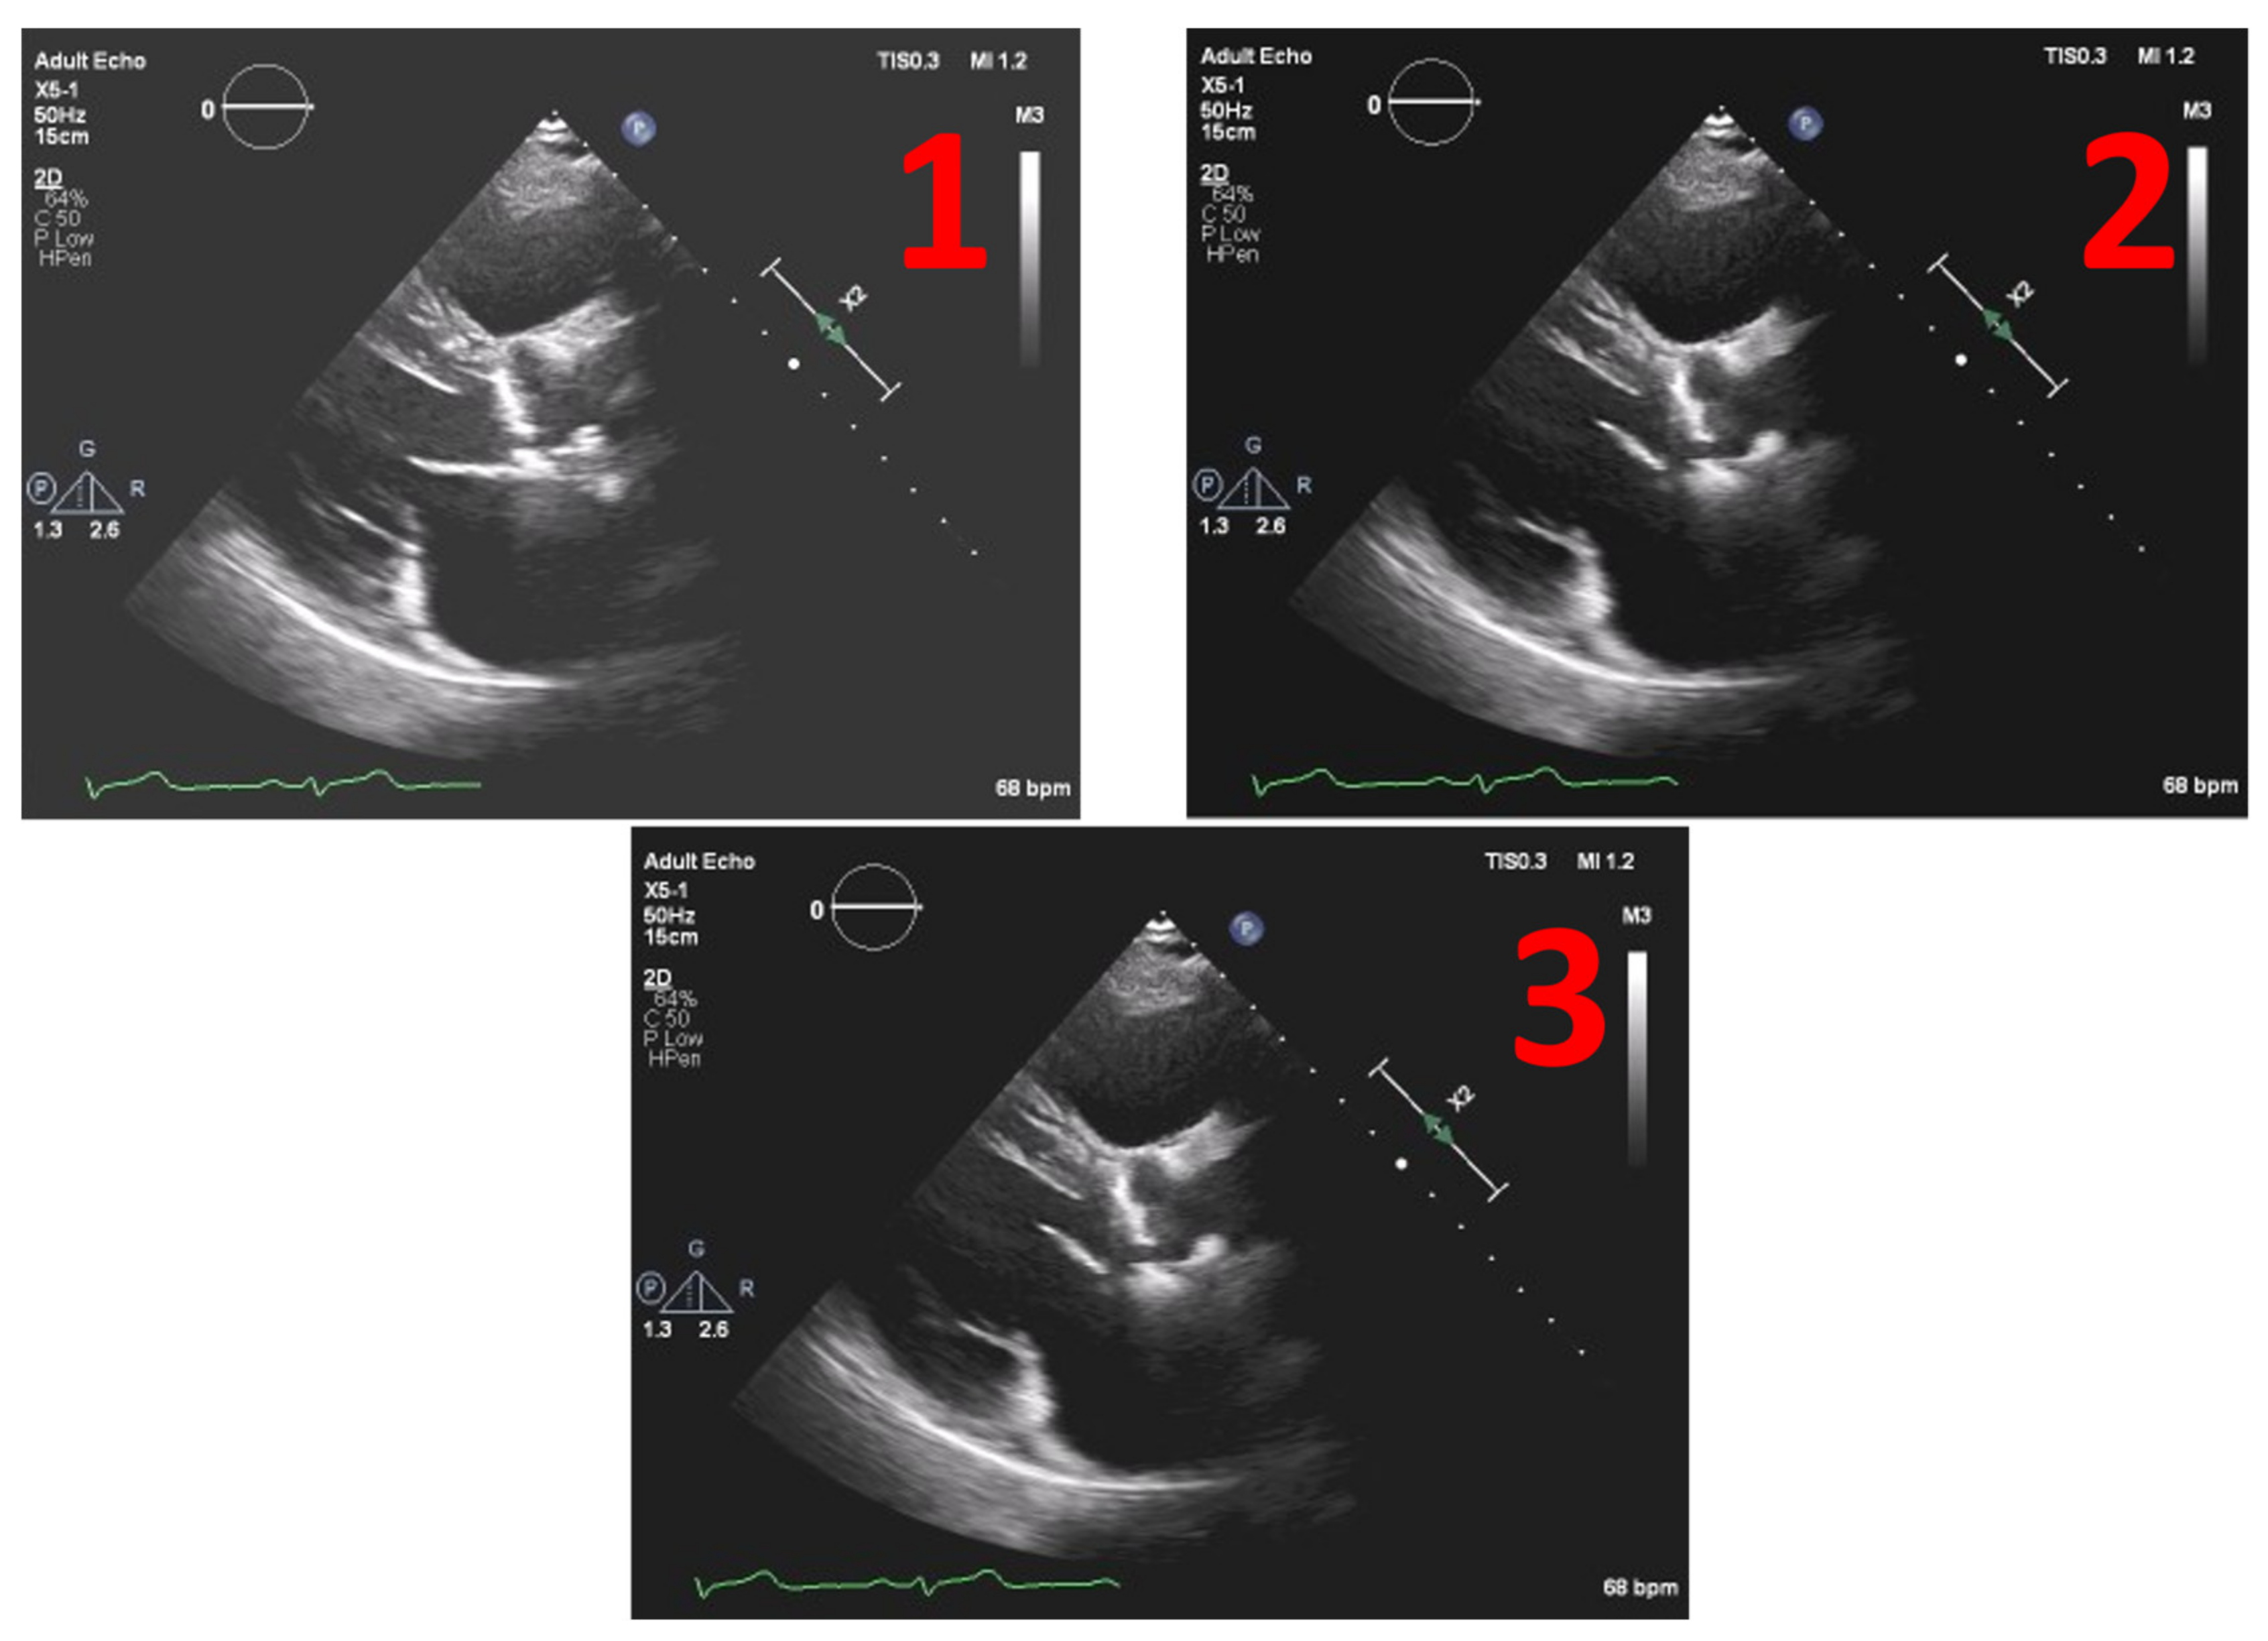

This method was tested on several images. Figure 8 depicts the example of one echocardiography with the most used different types of gains set in a post-processing stage, with the settings Window Width fixed at 250 and Window Level (WL) permuting between 75, 100 and 125.

Figure 8. Echocardiography examples with different Windrow Levels (WL) and fixed Window Width of 250 (1) WL = 75, (2) WL = 100, and finally, (3) WL = 125.